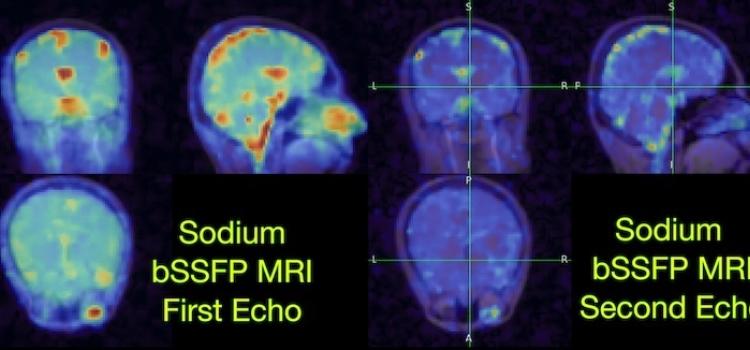

Dec. 1, 2025 — Researchers at the University of California, Berkeley and University of California, San Francisco have ...